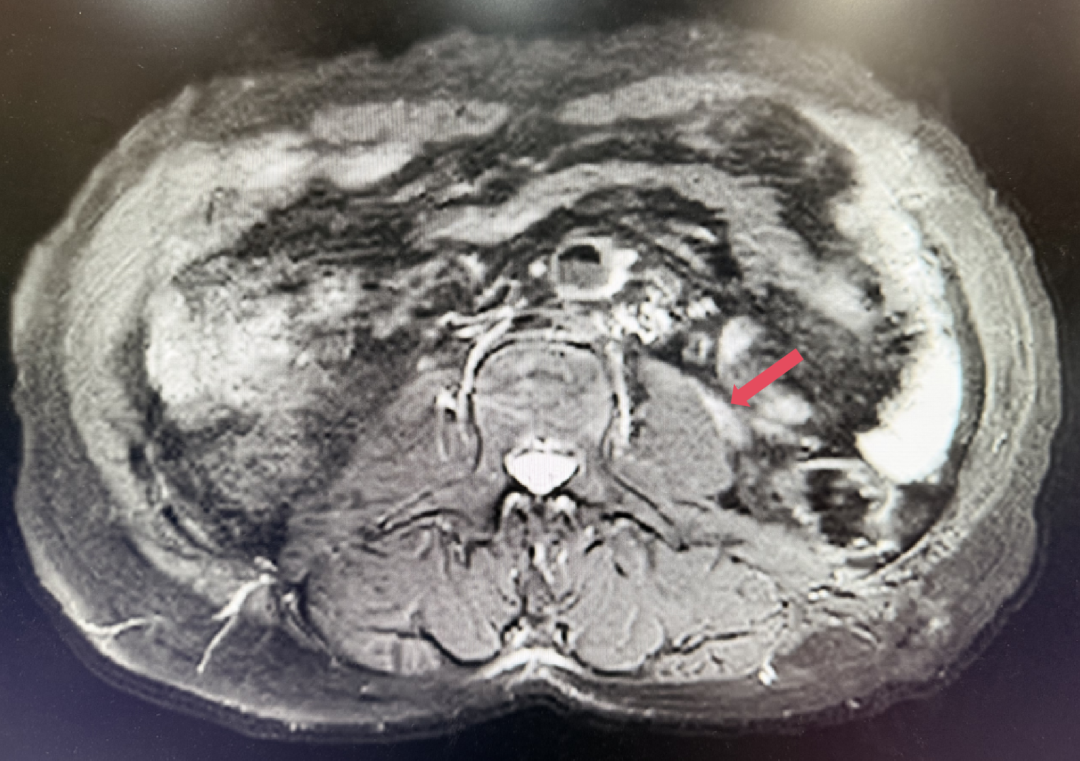

2023年1月开始使用呋喹替尼联合信迪利单抗方案,具体方案为:呋喹替尼5mg,po,qd,D1-14+信迪利单抗200mg,ivgtt,D1,q3w。患者基线肿瘤负荷为128.5mm。

2023年3月:用药6周(C2)后首次肿评,肿瘤负荷减少至76.8mm,达到PR。

2023年1月,基线